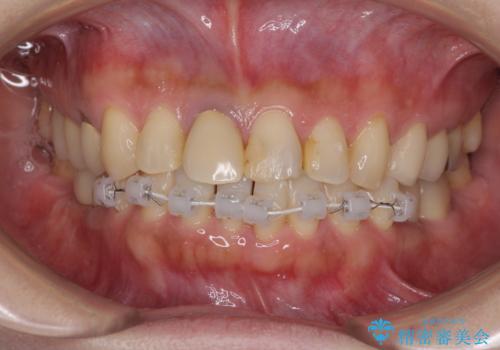

- 右下の欠損部の治療を希望して来院された患者様です。

部分矯正を行った後にインプラント埋入と手前の歯の根管治療を行い、その後補綴治療を行うこととしました。

治療途中より、上の歯や反対側の銀歯、上顎前歯の色合いや下顎前歯のデコボコが気になってきたため、全てを治療することとしました。